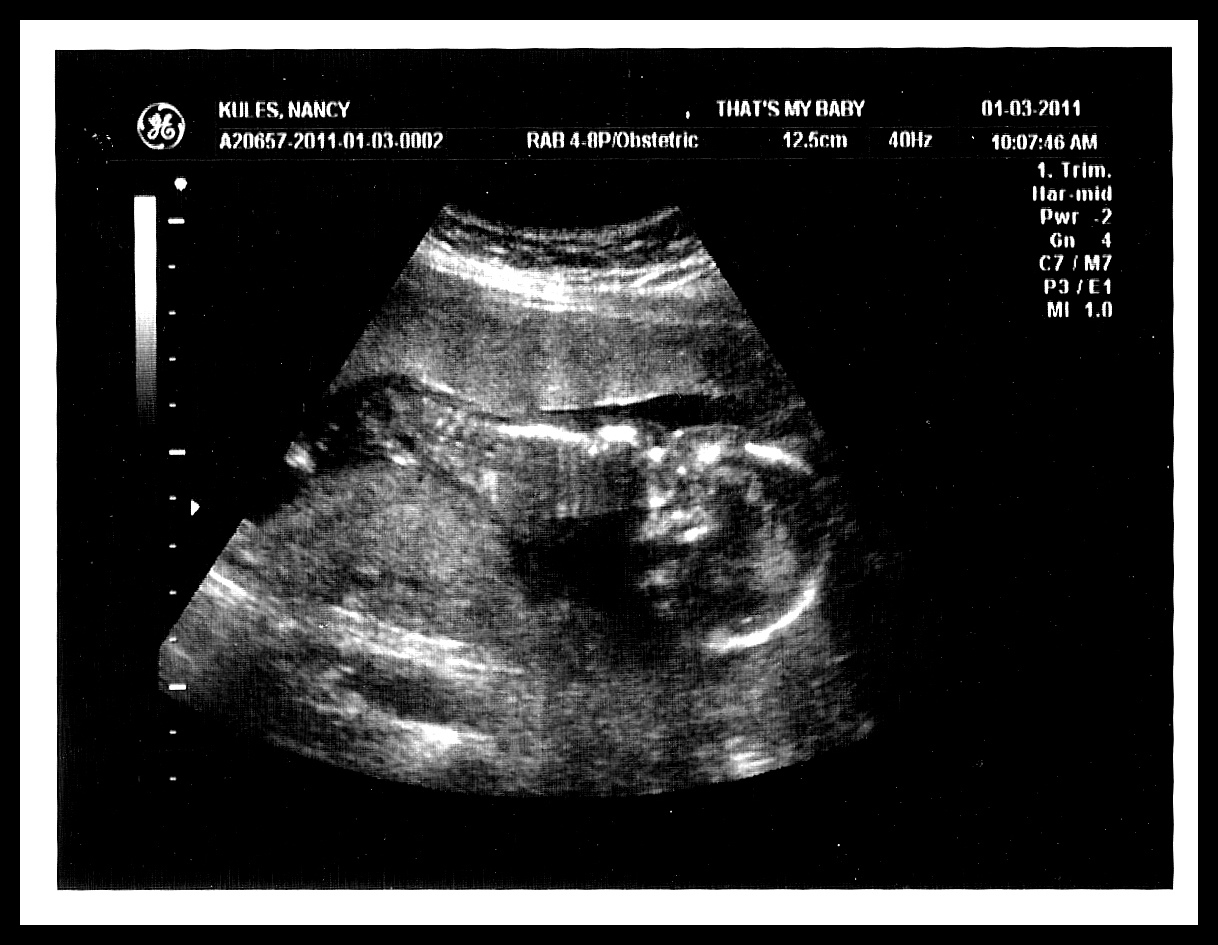

See the little bulge to the right of that leg? That's a penis/scrotum. The other leg is off to the right a little bit.

No genitals here, but you can see his spine along the top pretty well:

Another cool one of his LONG leg! The technician kept commenting on how BIG he is. She said: "Wow! That's a huge head. Oh my, his hand is giant! Wow, were your other babies huge? Look how LONG his arms and legs are!!!"

And finally, another decent shot of the "boy parts".